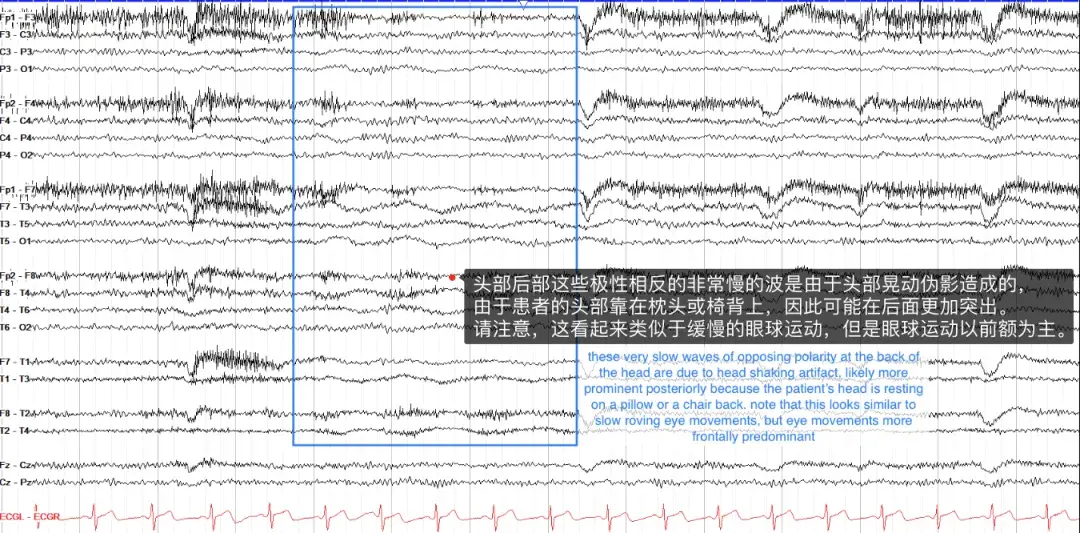

② 运动伪影(motion artifacts)

运动伪影具有多种外观,通常看起来混乱、高强度活动,不模仿任何实际的大脑模式。其中,摇头伪影可能稍微棘手一些,其特点是缓慢、低幅度的活动,如果患者将头枕在枕头上,这种活动通常在后方更为明显。它看起来类似于困倦时的眼球游动,但眼球运动是在前导联中。